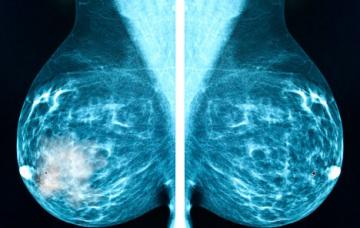

Diagnóstico del cáncer de mama

La detección precoz del cáncer de mama se basa en autoexploración y mamografía. Conoce los signos sospechosos de malignidad y otras pruebas diagnósticas.